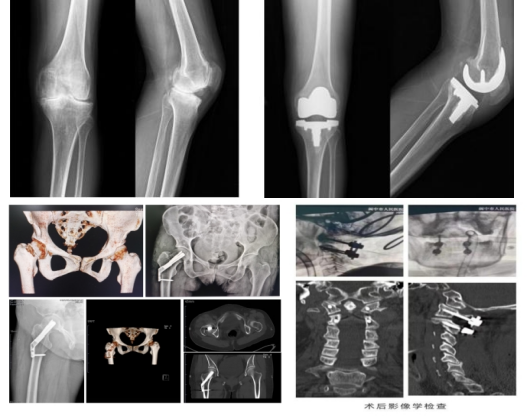

关节专业组 人工全髋关节置换术,人工股骨头置换术,人工全膝关节表面置换术(TKA),膝关节单髁置换术,人工关节置换术后翻修手术,人工肩关节置换术,人工桡骨头置换术,各种骨肿瘤及骨病的手术治疗;关节镜下滑膜清理、游离体取出,半月板修复及切除,膝关节前后交叉韧带重建,内外侧副韧带修复术,肩关节镜下修补肩袖损伤等;

脊柱专业组 颈椎骨折、脱位的前路手术(ACDF,经前路颈椎间盘切除椎间融合术/ACCF,颈椎前路椎体次全切、钛网植骨融合、钢板内固定)、后路手术(关节突切除、侧块螺钉内固定术)治疗;颈脊髓损伤的手术治疗(椎板切除术、后路单开门手术);胸腰椎骨折经后路钉棒系统内固定,老年骨质疏松性骨折的微创手术治疗(PKP,经皮穿刺球囊扩张椎体成形术);微创通道下腰椎间盘摘除术,腰椎椎管狭窄症及腰椎滑脱症的手术治疗(TLIF、PLIF、mis-TLIF),椎管内肿瘤切除术,胸腰椎陈旧性骨折不愈合的手术治疗;

创伤专业组 开展MIPPO技术(微创经皮钢板植入术)、长骨骨干骨折交锁髓内钉内固定术、股骨粗隆间骨折PFNA内固定技术、开放性骨折支架外固定技术、骨盆骨折及髋臼骨折重建钢板及螺钉内固定术、闭合复位骶髂螺钉内固定术、四肢骨折钢板或螺钉内固定术;对四肢陈旧性骨折,骨折不愈合、内固定失败等疑难病症有独到的治疗方法;